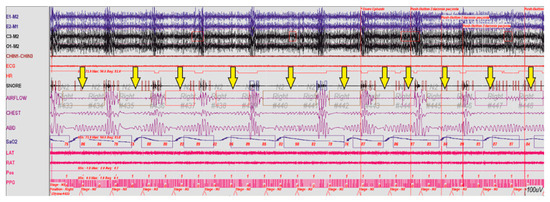

By detecting the risk of OSAS, we can indirectly prevent its development. Currently, the diagnostics of patients with sleep breathing disorders consists of conducting otolaryngologic or videoscopic examinations, as well as imaging studies (CT) and so on. A polysomnographic examination, colloquially also known as ‘sleep study’ consists of many procedures such as Electrocardiography (ECG), Electrooculography (EOG), Electroencephalography (EEG), Surface Electromyography (SEMG), Pulse Oximetry and oxygen saturation (SpO2). One of the elements of this study is monitoring patient’s respiratory activity. A fragment of a recorded polysomnographic examination is presented in Figure 15.

Figure 15.

Fragment of a polysomnographic examination of a patient with breathing disorders during sleep, the arrow marks episodes of apnea.

The information provided by the analysis of the presented case indicates the occurrence of numerous episodes of sleep apnea. As respiration stopped the blood oxygenation (SpO2) also decreased. The described device has a feature to continuously monitor the breathing action and to warn when such a situation occurs. Part of the recorded breath action can be seen in Figure 16, where two nostrils breathing were monitored. The apnea episode is marked with the red color, breath in and out, respectively, with blue and yellow.